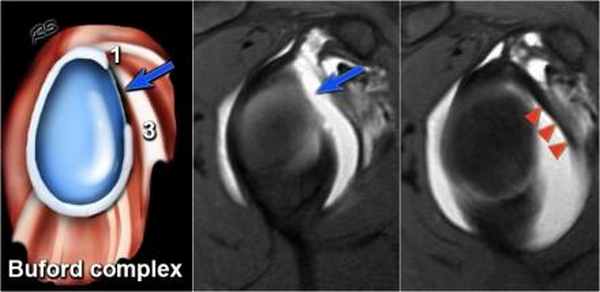

На первом из трех рисунков в корональной плоскости представлен нормальный вариант развития комплекса двуглавой мышцы и суставной губы. При первом типе комплекс двуглавой мышцы и суставной губы прочно крепится к суставной впадине. Видна неглубокая борозда между суставной впадиной и верхней губой, второй тип строения комплекса двуглавой мышцы и суставной губы. Обратите внимание, что борозда ниже губы соответствует контуру подлежащего суставного хряща. Это помогает отличить ее от разрыва: разрыв выступает за пределы хряща в структуру губы. Показана глубокая борозда между суставной впадиной и двуглавой мышцей/губой. Верхняя суставная губа имеет менисковидный тип строения. Глубокая борозда часто продолжается кпереди как сублабральное отверстие. У этого пациента верхняя губа крепится к подлежащему суставному хрящу Обратите внимание, что суставной хрящ изгибается медиально и простирается на верхний край костной части суставной впадины ниже места прикрепления длинной головки двуглавой мышцы плеча к суставной губе. У другого пациента визуализируется сублабральное углубление, создающее так называемый менисковидный вид верхней губы. Видимая ширина углубления изменяется при растяжении сустава. Для дифференцировки между углублением и повреждением верхней суставной губы лопатки спереди назад строение более важно, чем измерение ширины: углубление имеет ровные контуры, в то время как линия повреждения-неровный и зазубренный контур. На этом снимке плечо ротировано кнутри. Вследствие этого горизонтальная часть двуглавой мышцы ориентирована сагиттальнее и место прикрепления длинной головки двуглавой мышцы плеча к суставной губе имеет V-образную форму. Визуализационная картина места прикрепления двуглавой мышцы к губе различна, и зависит от ротации плеча. Визуализация суставной губы и капсулы значительно зависит от ротации руки. Внутренняя ротация, визуализируемая на данном снимке на уровне середины суставной впадины, приводит к растяжению переднего суставного кармана. Средняя суставно-плечевая связка очерчена жидкостью. Ротация кнаружи на том же уровне опустошает передний карман и уменьшает видимость средней суставно-плечевой связки, которая приближается к подлопаточной мышце. Теперь задний карман заполнен контрастом и выглядит растянутым. Максимальная ротация кнаружи позволяет визуализировать нормальный задний суставной карман. Средняя суставно-плечевая связка растянута и напряжена.

Подгубное углубление

Есть 3 типа прикрепления верхних отделов суставной губы в области 12 часов, в месте прикрепления сухожилия длинной головки двуглавой мышцы плеча.

I тип - между суставным хрящем суставной впадины лопатки и суставной губой нет углубления

II тип - есть маленькое углубление

III типа - есть крупное углубление

Это подгубное углубление тяжело отличить от SLAP повреджения или подгубного отверстия.

Эта иллюстрация показывает различие между подгубным углублением и SLAP-повреждением.

Углубление больше 3-5 мм всегда не нормально и должно трактоваться как SLAP-повреждение.

Это изображение показывает типичные изменения при сублабральном углублении.